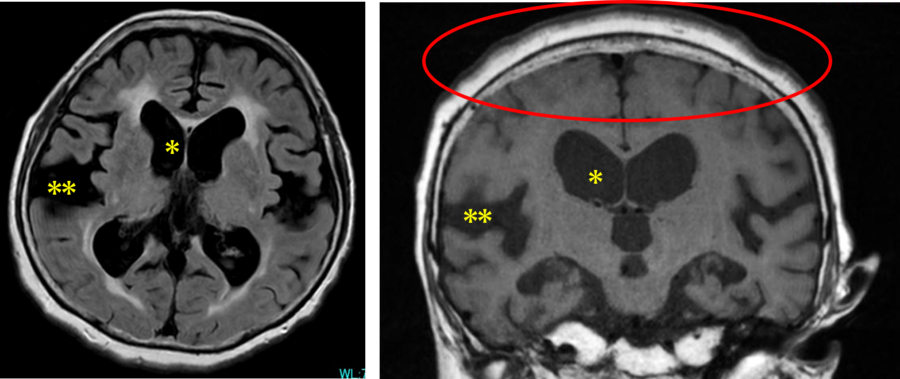

水頭症のひと 脳神経外科の病気:水頭症 | 病気の治療 | 徳洲会グループの詳細情報

脳神経外科の病気:水頭症 | 病気の治療 | 徳洲会グループ。特発性正常圧水頭症(とくはつせいせいじょうあつすいとうしょう。診断と検査|高齢者の水頭症 iNPH.jp。iNPHとは?|高齢者の水頭症 iNPH.jp。絵画の種類...油彩画・油絵形式...掛け軸・掛軸主題...人物・肖像壁掛けアート贄田越郎画主な画材...油彩絵の具